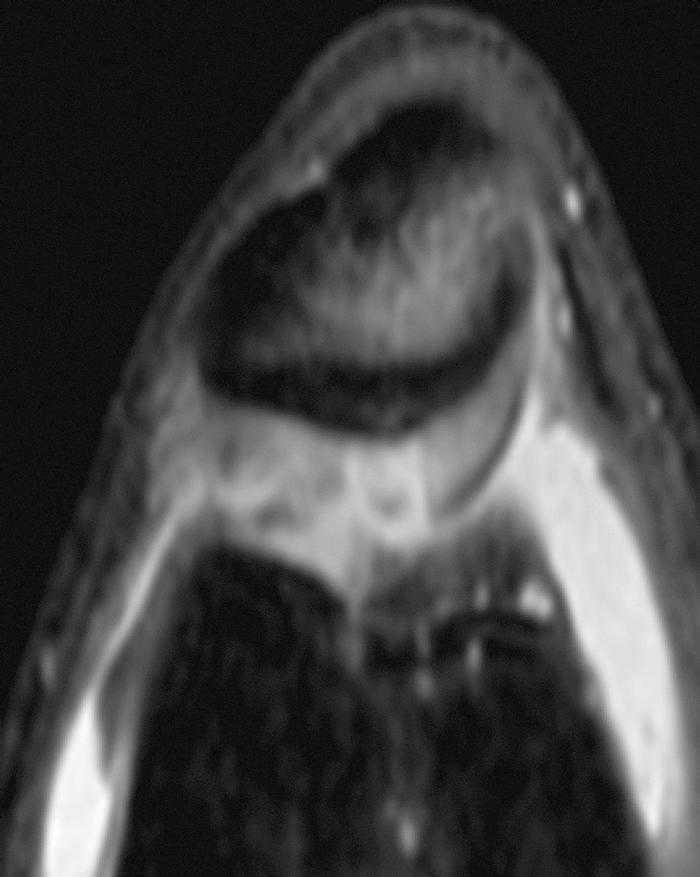

La RM muestra (figs. 1, 3 y 5):

Figura 5 RM. Imagen potenciada en T1. Cuerpos libres alrededor de los ligamentos cruzados y en otras localizaciones intraarticulares.

• Múltiples cuerpos libres intraarticulares.

• Ligamentos y meniscos y resto de estructuras íntegras.